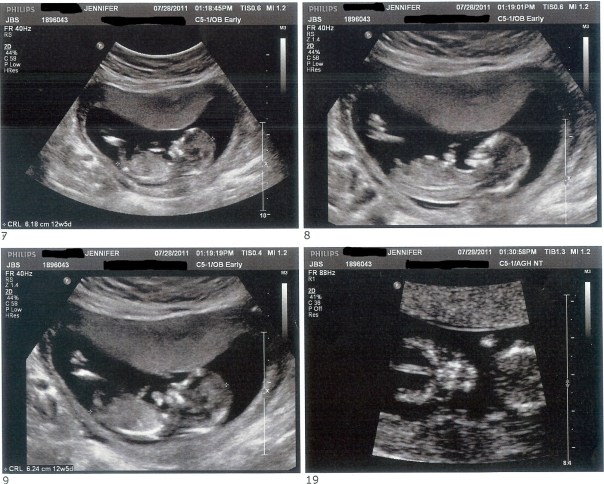

The following day we had my Nuchal Translucency scan. It’s a test that can only be done between 11 and 13 weeks where they measure the back of the baby’s neck to see if it’s thickened which is common in babies with Down Syndrome. They also do a blood test and these two tests together will tell you the risk factor for your baby. We just like to get an extra peek at the baby and 12 weeks is such a great time for an ultrasound because the little ones are moving like crazy even though you can’t feel it and they have tons of space to bounce around it.

I was 12 weeks 4 days at this scan (I was 12w1d at Adaline’s scan) and this baby was completely different from Adaline. Adaline moved like crazy…so much so that it took them the longest time to get her calm enough to measure her neck. She literally bounced off of the walls of my uterus and did flips and everything. This baby was very laid back. The movements were all small wiggles and hand movements, nothing big. It was so interesting to see how different this baby was compared to my daughter. Even though this baby stayed pretty still (s)he was still in the wrong position for the test and we had the opposite problem. The tech had me coughing and smacking my belly to try to get the baby to move into a different position and each time it would just fidget every so slightly as if to say, “Leave me alone! 5 more minutes, mom!”

We asked the tech if she could give us and educated guess on gender. She said that if she had to guess she’d say that it’s a…boy! But she also said that it’s much too early to tell (I knew that already) and that she’s been wrong before at this point. At Adaline’s nt ultrasound they “guessed” girl and obviously they were right, but at my nephew’s nt ultrasound they also “guessed” girl and obviously they were wrong…so a nt gender guess is still 50/50. We’ll be able to find out pink or blue in mid-September.

Right after the scan they let me know that the neck looked normal but to remember that the blood test is important and then I went upstairs to have blood drawn. I’ve read online that many women get a finger prick for this test but both times I’ve had blood drawn from my arm. The hospital called a few days later to let me know that all of the test results looked normal and to give me the risk factor, which I don’t remember the exact number, but it was very low.